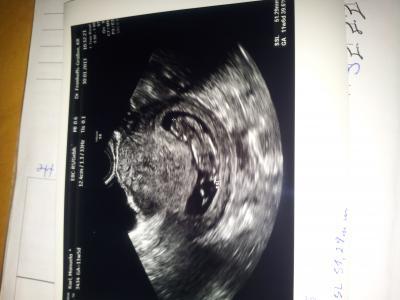

FA ist sehr zufrieden mit krümel und mit mir *grins Krümel ist jetzt 51,29mm groß.und alles Drann aber seht selbst.. und sooo süß....hänge mal n Bildchen an Axo bin heute 11+5

Bild zu zurück vom FA... - Forum für August - Mamis